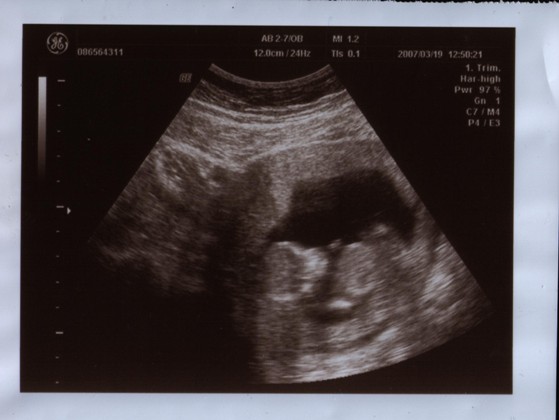

Várjuk a uh képet. Tényleg nagyon cuki a kislányod a képen.